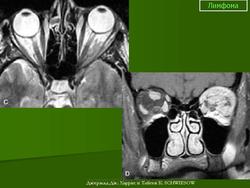

Диагноз злокачественной лимфомы орбиты труден. Из инструментальных методов исследования более информативны ультразвуковое сканирование, компьютерная томография (рис. 20.24, в) и тонкоигольная аспирационная биопсия с цитологическим исследованием. Необходимо обследование у гематолога для исключения системного поражения. Наружное облучение орбиты — практически безальтернативный высокоэффективный метод лечения. Полихимиотерапию подключают при системном поражении. Эффект лечения проявляется в регрессии симптомов патологического процеса в орбите и восстановлении утраченного зрения. Прогноз при первичной злокачественной лимфоме для жизни и зрения благоприятный (83 % больных переживают 5-летний период). Прогноз для жизни резко ухудшается при диссеминированных формах, но частота поражения орбиты при последних составляет чуть более 5 %.